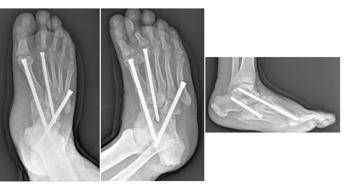

(Adnkronos) – Uno dei più temibili nemici del piede è una grave e rara complicanza del diabete, un capitolo del cosiddetto piede diabetico, con un nome complesso: la neuro-osteoartropatia di Charcot. Il Policlinico universitario Gemelli Irccs di Roma è una delle poche strutture italiane dove è possibile gestirla da un punto di vista internistico e diabetologico ed effettuare i complicati interventi di salvataggio ortopedico di questi piedi deformati e disabilitati dalla malattia. Sono molteplici gli interventi eseguiti al Gemelli ogni anno per restituire la possibilità di camminare, scongiurando il rischio amputazione, a diverse persone con diabete. Se intercettata precocemente, la malattia non progredisce verso la fase cronica, quella appunto delle deformità articolari. Ma per questo è necessario un occhio esperto, quello del diabetologo. "Condizione predisponente del piede di Charcot – spiega Dario Pitocco, associato di Endocrinologia all'università Cattolica del Sacro Cuore Campus di Roma e direttore della Uosa di Diabetologia della Fondazione Policlinico Gemelli – è la neuropatia diabetica, che comporta un grave quadro di disregolazione infiammatoria, concentrato a livello del piede. Ma questa è solo una parte della storia. La neuropatia è importante, ma non basta da sola e le vere cause del piede di Charcot di fatto non sono ancora note. Potrebbe giocare un ruolo anche una predisposizione genetica sulla modulazione del metabolismo dell'osso". A essere affetto da neuropatia è almeno il 30-40% delle persone con diabete; il piede di Charcot compare solo nello 0,05% dei casi. Parliamo dunque di una malattia rara. "Questi pazienti – prosegue Pitocco, co-autore anche di una Consensus dell'American Diabetes Association sull'argomento – hanno una grave disregolazione dei processi infiammatori, anche a seguito di uno stimolo banale come il sovraccarico sul piede. Molto spesso sono colpite persone che passano molto tempo in piedi (camerieri, cuochi) o che utilizzano molto il piede come gli autisti. Il fatto che la neuropatia attutisca il dolore, che in genere è un importante campanello d'allarme, fa sì che la diagnosi sia tardiva. Nelle fasi iniziali (acute) il piede appare rosso, gonfio, caldo, ma non è presente dolore. Un occhio non esperto può scambiare il quadro per una vasculite, per un trauma o per gotta. Oltre alla visita specialistica diabetologica, che permette di porre il sospetto diagnostico, un esame strumentale importante nella fase acuta è la risonanza magnetica, che evidenzia edema della spongiosa dell'osso. Una semplice radiografia nella fase iniziale, invece, non consente di fare diagnosi. In questa fase l'approccio terapeutico più efficace è il riposo; il paziente non deve caricare su quel piede (vengono utilizzati speciali tutori per evitare il carico)". Se questa fase diagnostica viene mancata, la malattia progredisce anche rapidamente (pochi mesi) verso la fase cronica, quella delle complicanze che richiedono l'intervento dell'ortopedico. E non solo. La gestione del piede di Charcot richiede un'équipe multidisciplinare, perché oltre al diabetologo e all'ortopedico spesso è necessario l'intervento del chirurgo vascolare, dell'infettivologo, del chirurgo plastico, del dermatologo, del fisioterapista e di tanti altri specialisti. "Nel piede di Charcot – descrive Carlo Perisano, ricercatore in Ortopedia e Traumatologia all'università Cattolica Campus di Roma e dirigente medico presso la Uoc di Ortopedia e Traumatologia del Policlinico Gemelli – assistiamo a una progressiva alterazione dei tessuti molli, delle articolazioni e delle ossa del piede, che vanno incontro a un marcato riassorbimento e a molte microfratture che portano all'instaurarsi delle deformità. Il piede si deforma fino a diventare un 'piede a dondolo' (in inglese 'rocker bottom foot deformity'), a causa della mal consolidazione dell'osso e a una stabilizzazione di quella deformità che determinano una serie di sequele". Queste, in stadio avanzato, possono essere corrette solo da un complesso intervento, che di fatto diventa una chirurgia di salvataggio dell'arto. "Sono interventi che mirano a correggere deformità estremamente complesse del piede e della caviglia – illustra Perisano – e che prevedono una serie di procedure chirurgiche (nell'ambito dello stesso intervento), quali osteotomie correttive e successive osteosintesi. Questo consente la ricostruzione di un asse del piede e della caviglia, per permettere al paziente di tornare a camminare (in genere entro un paio di mesi dall'intervento). I pazienti affetti da questa condizione infatti non riescono più a deambulare perché queste deformità comportano alterazioni dell'appoggio, che sottopongono alcune zone del piede, normalmente non deputate a sostenere il carico, ad una pressione eccessiva che a sua volta può portare ad ulcerazioni; queste, nei pazienti diabetici (che spesso sono anche vasculopatici), possono causare infezioni gravi e profonde, che a loro volta comportano un elevato rischio di amputazione". "Il piede di Charcot – commenta Giulio Maccauro, ordinario di Ortopedia alla Cattolica Campus di Roma e direttore della Uoc di Ortopedia e Traumatologia del Gemelli – è una condizione clinica estremamente invalidante. All'interno della nostra istituzione riusciamo a dare risposte, all'interno di un percorso multidisciplinare, a tutte le persone con piede diabetico, offrendo loro l'intera gamma di trattamenti ortopedici, da quelli convenzionali ortesici agli interventi chirurgici più avanzati".